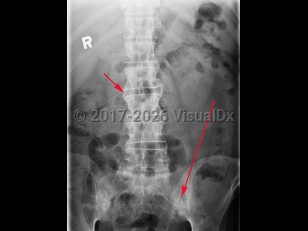

Ankylosing spondylitis

Ankylosing spondylitis is an autoimmune inflammatory disorder characterized by inflammation of the axial skeleton and peripheral joints. It typically begins in the second or third decade of life with a male-to-female prevalence of 2-3:1. There is a high concordance of ankylosing spondylitis in patients with haplotype human leukocyte antigen B27 (HLA-B27).

Patients most typically present with dull pain in the lower lumbar or gluteal region accompanied by early morning stiffness that improves with activity but not with rest. As the disease progresses, pain becomes persistent and bilateral and may worsen at night. Cervical ("chalk-stick") fractures may occur, especially after trauma. In addition to back pain, enthesitis (tenderness at the tendon or ligamentous insertion site to bone) may be common at the costosternal junction, spinous processes, iliac crests, greater trochanters, ischial tuberosities, tibial tuberosities, and heels. Approximately 30% of patients experience arthritis of peripheral joints other than the hips and shoulders. The most common extraarticular manifestation is acute anterior uveitis in up to 40% of patients. A large percentage of others may have inflammation of the terminal ileum or colon, although the majority of cases are asymptomatic. Only a minority of these patients progress to develop inflammatory bowel disease.